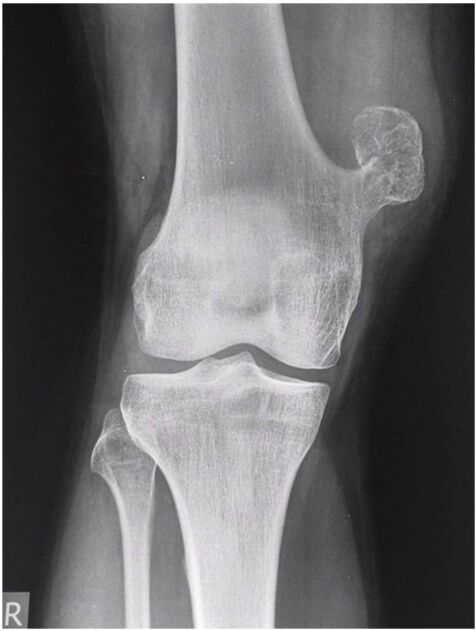

9.根據《中醫外科講義》關於虛證鶴膝風的敘述,下列何者正確?(A)由足三陰虧損,風寒濕入絡化熱所致(B)初起膝腫而如棉,皮色微紅,焮熱光亮(C)疼痛日增,及至數月以後,漸感屈伸不利,行走無力(D)如腫潰後時出白漿膿,可用硇砂散蓋貼,不難平復而癒